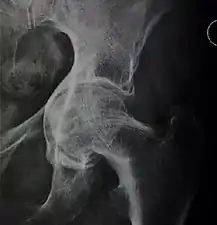

In 1979 Dr. John F. Crowe et al. proposed a classification to define the degree of malformation and dislocation. Grouped from least severe Crowe I dysplasia to most severe Crowe IV.[13] This classification is very useful for studying treatment results.

Rather than using the Wiberg angle because it makes it difficult to quantify the degree of dislocation they used 3 key elements to determine the degree of subluxation: A reference line at the lower rim of the "teardrop", junction between the femoral head and neck of the respective joint and the height of the pelvis (vertical measurement). They studied anteroposterior pelvic x-rays and drew horizontal lines through the lower rim of a feature called "teardrop". The distance between this line and the middle lines of the junction between femur head and neck gave them a measure of the degree of femur head subluxation. They further established that a "normal" diameter of the femur head measures 20% of the height of the pelvis. If the middle line of the neck-head junction was more than 10% of the pelvis height above the reference line they considered the joint to be more than 50% dislocated.[13]

The following types resulted:[13]